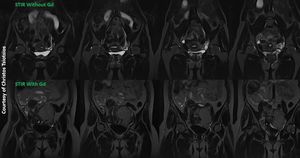

STIR stands for Short-TI Inversion Recovery and is typically used to null the signal from fat. STIR sequence is generally uniform and relatively independent of magnetic field inhomogeneities. Unfortunately, STIR cannot be used as a fat suppression technique post-gadolinium (figure). STIR does not specifically suppress fat; it only suppresses tissues with (short) T1 values in the range of fat (200-300 ms). Thus gadolinium-containing tissues (like bladder, uterine fibroid; bottom row) with similar relaxation times will also be suppressed.